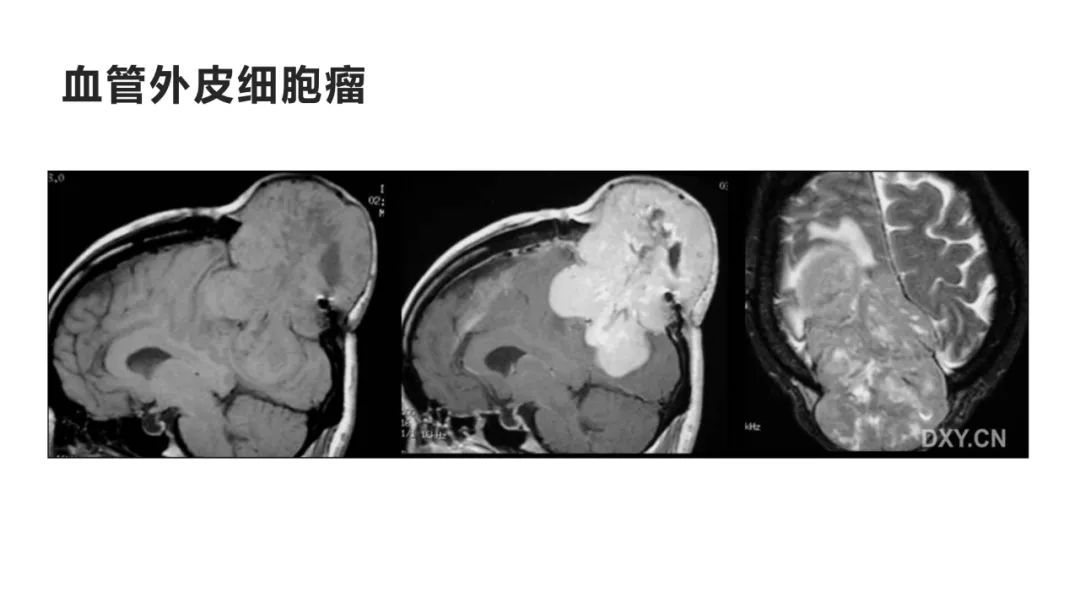

颅脑影像诊断基础知识讲座:颅骨病变